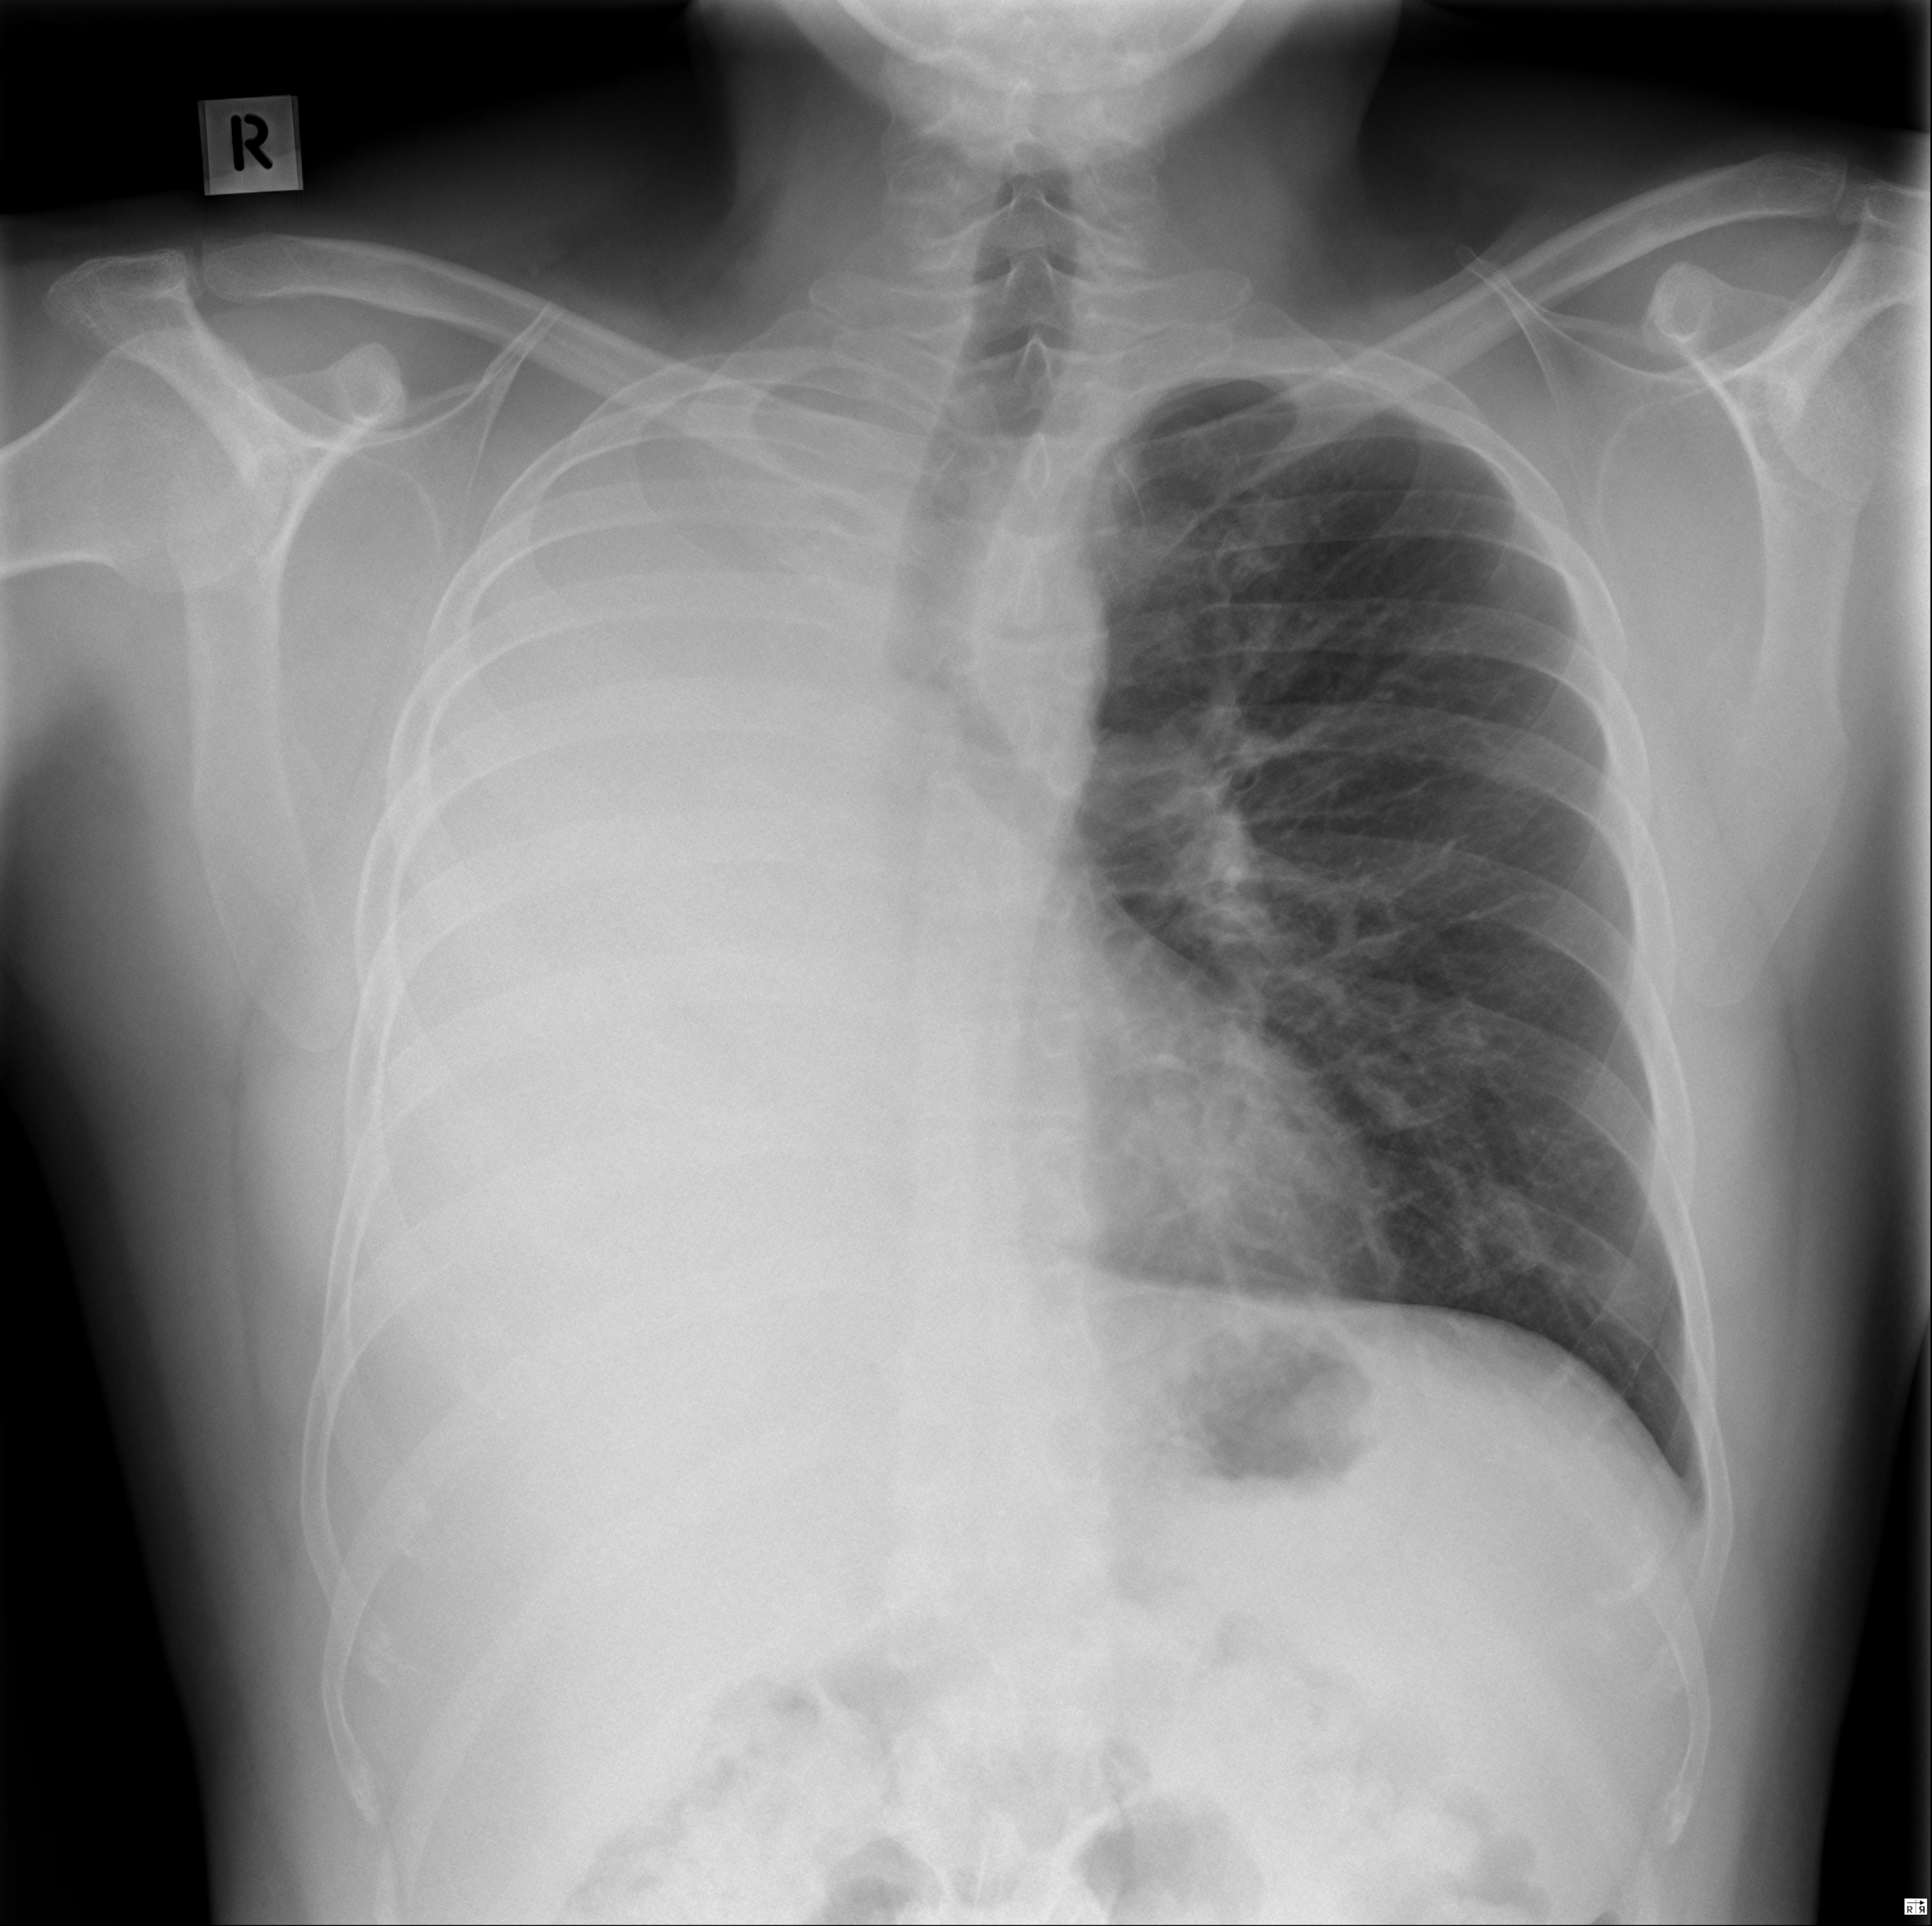

Рентгенодиагностика бронхопневмонии: Советы и примеры

Раздел: Альбом открытий